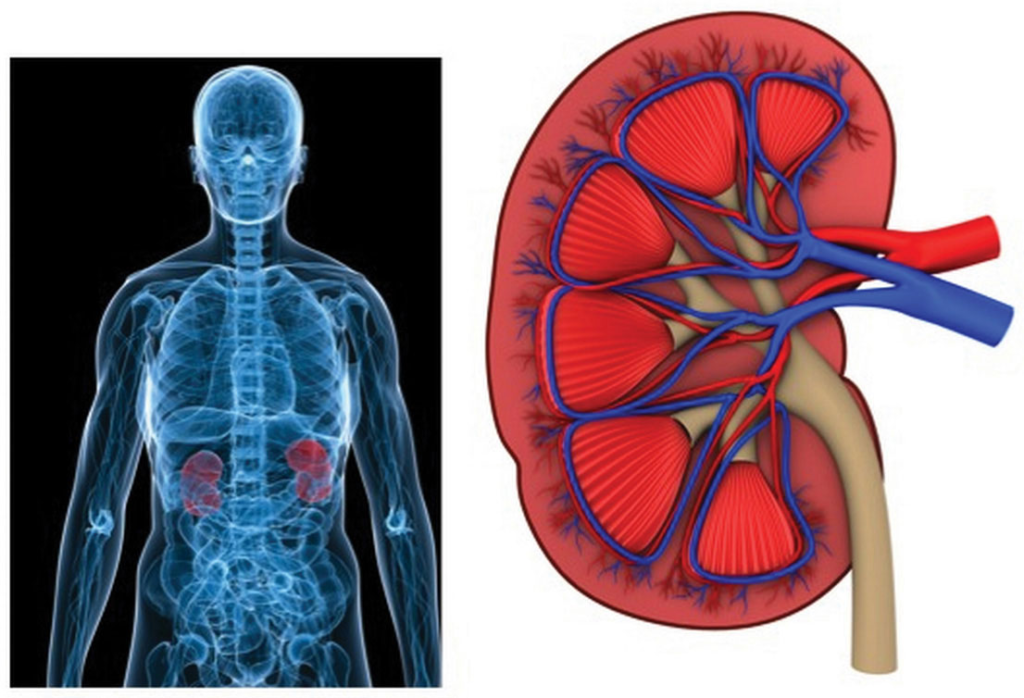

Tot slot kunnen onderliggende situaties, zoals een verminderde nierfunctie of verminderde hartfunctie, van invloed zijn op het vasthouden van vocht in het lichaam.

Door elke dag voldoende water te drinken, zorg je ervoor dat je lichaam gehydrateerd blijft en de nieren optimaal kunnen functioneren.

Dit helpt bij het afvoeren van overtollig natrium en gifstoffen, waardoor het vasthouden van vocht aanzienlijk wordt verminderd.